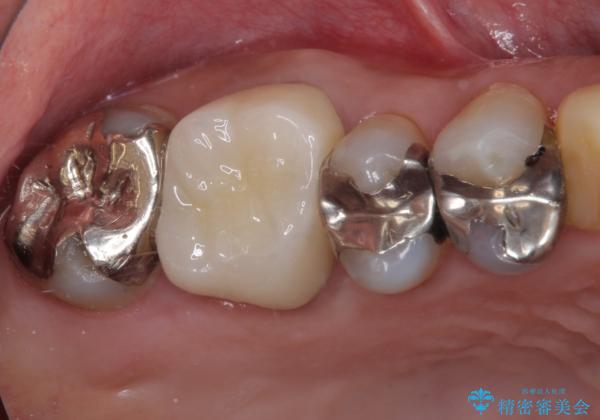

- 右上の小臼歯部に咬んだときに強い痛みを感じるとのことで来院された患者様です。

診査を行った結果、根管治療を行った後にオールセラミッククラウンにて補綴する治療計画となりました。

咬んだときの痛みに加えて夜間のズキズキする痛みもありましたが、1回目の根管治療実施後間もなく咬んだときの痛みがなくなったので、2回目に根管充填を行いました。